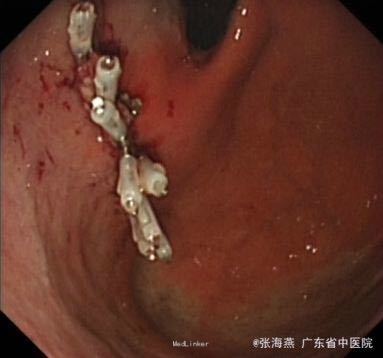

诊断:1.胃底间质瘤(ESD术后);2、慢性胃炎;3、高血压病2级;4、颈椎退行性变。 治疗:治疗上,行ESD术切除胃底肿物,术后予明可欣静滴预防感染,潘妥洛克静滴抑酸护胃,铝镁加混悬液口服保护胃粘膜,以及补液营养支持治疗。术后病理提示:符合胃肠道间质瘤(低级别,无风险);经治疗后,患者无特殊不适,予出院。

随访:ESD术后3月随访,患者无上腹部疼痛发作。 讨论:患者胃底间质瘤已完整切除,属低级别、无风险,就无需服用格列卫,嘱患者定期复查胃镜。